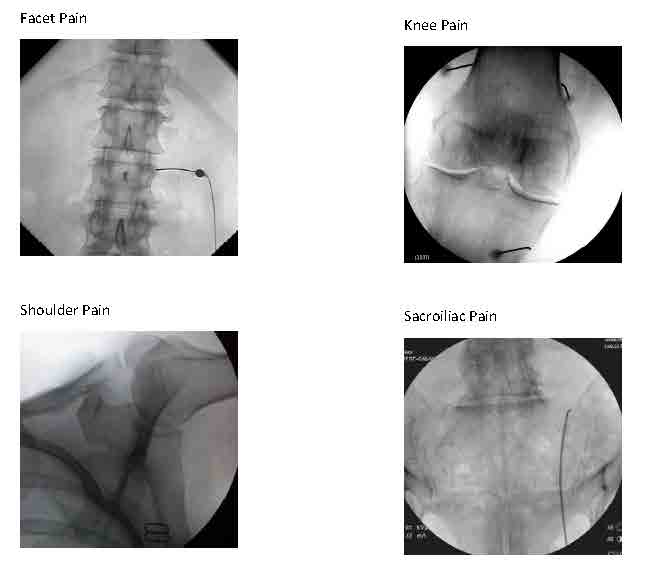

Sacroiliac joint (SIJ) pain is a common source of lumbosacral back pain that we can diagnose and treat with 2 types of fluoroscopically guided procedures:

- Sacroiliac joint steroid injections or

- Blocks of nerves to the SIJ with local anesthetic (for diagnosis) twice to determine if blocking long term with Radiofrequency Ablation/RFA (for treatment) is recommended.

Treatment with RFA tends to last around 9 months on average (give or take 3 months), which could be 2-4 times longer than the SIJ steroid injection. However, the steroid injection requires just one session that combines diagnosis and treatment, where the RFA procedure typically requires 3-4 sessions initially. If successful, future treatments with RFA can be repeated generally without the preliminary diagnostic blocks for recurrence of the same pain.

Depiction of a left sacroiliac joint injection